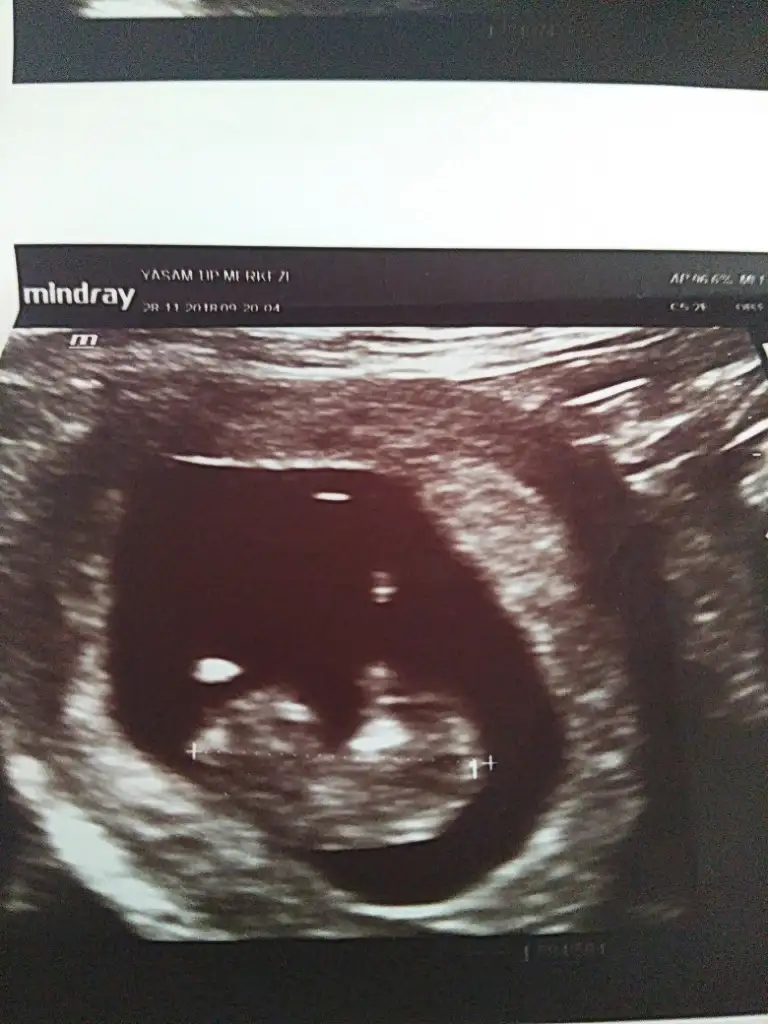

Ay maşallah kuzuya.Erkek gibi geldi bana :)kızlarr napıyorsunuz nasılsınız maalesef sayfa birikmiş okuyamadım hepsini biraz ara buldum iş yerinden foto atayım dedim yorum bekliyorum 10 haftalık ultrason fotosu koyucam kimin içinden ne geçiyo merak ediyorummm

Cnm hic bir fikrm yk masallah diyeyim dedm :)kızlarr napıyorsunuz nasılsınız maalesef sayfa birikmiş okuyamadım hepsini biraz ara buldum iş yerinden foto atayım dedim yorum bekliyorum 10 haftalık ultrason fotosu koyucam kimin içinden ne geçiyo merak ediyorummm